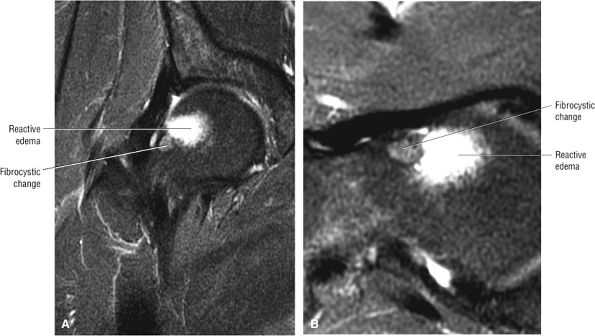

In DDH the labrum may be hypertrophic and associated with a femoral head chondral crease.

An anterosuperior cleft (Fig. 3.61) may be seen as a normal variant in the presence of a normal lateral acetabular labrum. On anterior coronal or sagittal images, this cleft is seen as a partial undercutting of the labrum on a single image. The extension of fluid into this cleft occurs from the femoral side. It may be more commonly seen in labral hypertrophy associated with mild developmental dysplasia of the hip (DDH).

An enlarged or hypertrophied labrum may occur in patients with mild DDH.17 We have observed a femoral head chondral crease (Fig. 3.66) in these patients, creating a demarcation trough medial to a femoral head bump immediately proximal to the physeal scar. Patients who demonstrate femoroacetabular impingement (or lateral acetabular rim syndrome in DDH) also have direct impingement between the lateral acetabular labrum and the femoral head.